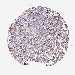

LUNG ADENOCARCINOMA (VALIDATION) - Interactive survival scatter ploti

The Survival Scatter plot shows the clinical status (i.e. dead or alive) for all individuals in the patient cohort, based on the same data that underlies the corresponding Kaplan-Meier plots. Patients that are alive at last time for follow-up are shown in blue and patients who have died during the study are shown in red.

The x-axis shows the expression levels (FPKM) of the investigated gene in the tumor tissue at the time of diagnosis. The y-axis shows the follow-up time after diagnosis (years). Both axes are complimented with kernel density curves demonstrating the data density over the axes. The top density plot shows the expression levels (FPKM) distribution among dead (red) and alive patients (blue). The right density plot shows the data density of the survived years of dead patients with high and low expression levels respectively, stratified using the cutoff indicated by the vertical dashed line through the Survival Scatter plot. This cutoff is automatically defined based on the FPKM cutoff that minimizes the p-score. The cutoff can be changed by dragging the vertical line or by entering a cutoff value in the square labeled "Current cut-off".

Under the Survival Scatter plot the p-score landscape (black curve; left axis) is shown together with dead median separation (red curve; right axis). Dead median separation is the difference in median mRNA expression between patients who have died with high and low expression, respectively. It is calculated as follows: median FPKM expression of dead patients with high expression - median FPKM expression of dead patients with low expression. This is intended to aid the user in visually exploring custom cutoffs and the associated p-scores and dead median separation.

Individual patient data is displayed and can be filtered by clicking on one or more of the category buttons on the top of the page. Categories describing expression level and patient information include: high, low, alive, dead, female, male and tumor stages. The scale of the x-axis can be toggled between linear and log-scale by clicking on the "x log" button. Mouse-over function shows TCGA ID, patient information and mRNA expression (FPKM) for each patient.

& Survival analysisi

Kaplan-Meier plots summarize results from analysis of correlation between mRNA expression level and patient survival. Patients were divided based on level of expression into one of the two groups "low" (under cut off) or "high" (over cut off). X-axis shows time for survival (years) and y-axis shows the probability of survival, where 1.0 corresponds to 100 percent.

ZNF709 is not prognostic in Lung Adenocarcinoma (validation)

Best expression cut offi

Based on the FPKM value of each gene, patients were classified into two groups and association between prognosis (survival) and gene expression (FPKM) was examined. The best expression cut-off refers the FPKM value that yields maximal difference with regard to survival between the two groups at the lowest log-rank P-value. Best expression cut-off was selected based on survival analysis .

: 0.83

P scorei

Log-rank P value for Kaplan-Meier plot showing results from analysis of correlation between mRNA expression level and patient survival.

N/A

5-year survival highi

5-year survival for patients with higher expression than the expression cutoff.

5-year survival lowi

5-year survival for patients with lower expression than the expression cutoff.

TCGA RNA samplesi

RNA-seq data is reported as average FPKM (number Fragments Per Kilobase of exon per Million reads), generated by the The Cancer Genome Atlas (TCGA) .

Normal distribution across the dataset is visualized with box plots, shown as median and 25th and 75th percentiles. Points are displayed as outliers if they are above or below 1.5 times the interquartile range. FPKM values of the individual samples are presented next to the box plot.

Average pTPM 1.4

Number of samples 105